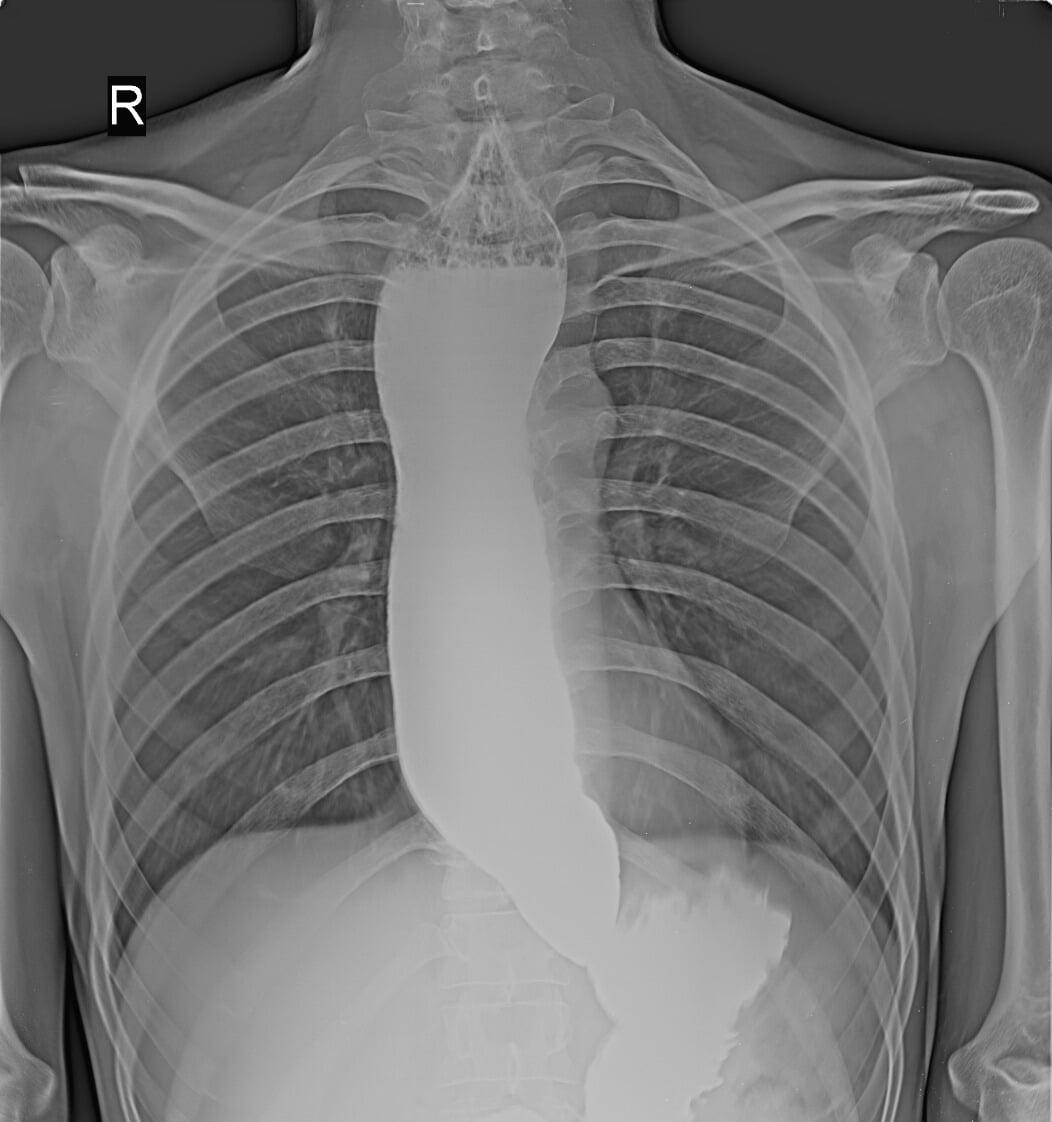

Barium Swallow

Dilated esophagus with narrowing at lower end s/o Achalasia Cardia